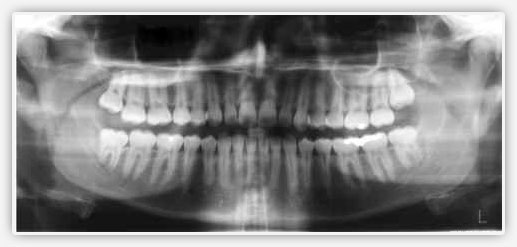

Röntgenler çoğunlukla, diş çürükleri, periodontal hastalıktan dolayı kemiğin zarar görmesi, diş apseleri, sıkışmış dişler, çene kemiğinde ve dişte kırılma ile dişler ve çene kemiğindeki diğer bozukluklarının varlığını ve boyutunu teşhis etmekte yararlıdır.

Mevcut olan dolguların altında gelişen çürük ve çatlak ya da diğer zararların fark edilmesine imkan verir.

Dişeti hastalığı nedeniyle oluşan kemik kaybı röntgen yardımı ile fark edilebilir.

İmplant hazırlığı ve yerleştirilmesinde, ortodontik tedavi ve bunların diş hekimliği çalışmalarında diş hekimi için yararlı ve gereklidir.

Kist, ağız kanserleri ve metabolik ve sistemik hastalıklarla birlikte oluşan değişikliklerin saptanması maksadıyla da kullanılır.

Röntgenlerin yardımı ile çocukların ağzındaki diş gelişimi ve büyümeleri takip edilir.

Enfeksiyon ya da sinirin ölmüş olması gibi kök kanalındaki sorunlar da röntgen yardımı ile görülebilir.